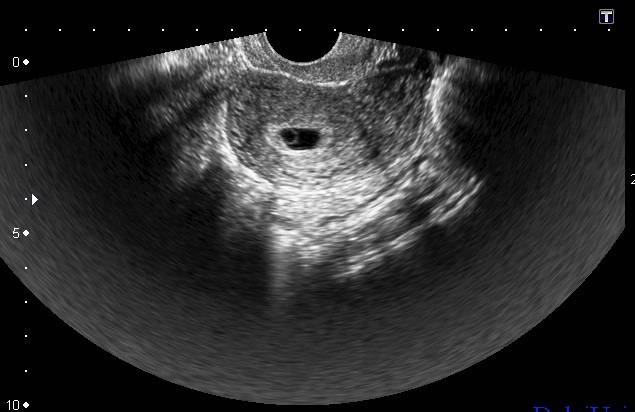

Существуют сроки беременности, в которые целесообразно измерять именно КТР — с седьмой по четырнадцатую неделю. Ранее специалист идентифицирует эмбрион в матке как округлое образование из одинаковых клеток — плодное яйцо. Позднее четырнадцати недель эмбрион уже настолько развит, что для определения его здоровья используются другие ультразвуковые показатели.

На ранних стадиях беременности определяют размеры плодного яйца

Ультразвук безопасен для организма беременной женщины и формирующегося в утробе плода. Несмотря на различные мифы, вреда даже многократная повторная диагностика не приносит. Исследование плода в ранние сроки беременности позволяет своевременно выявить возможные отклонения, выяснить причину и выработать дальнейшую лечебную тактику.